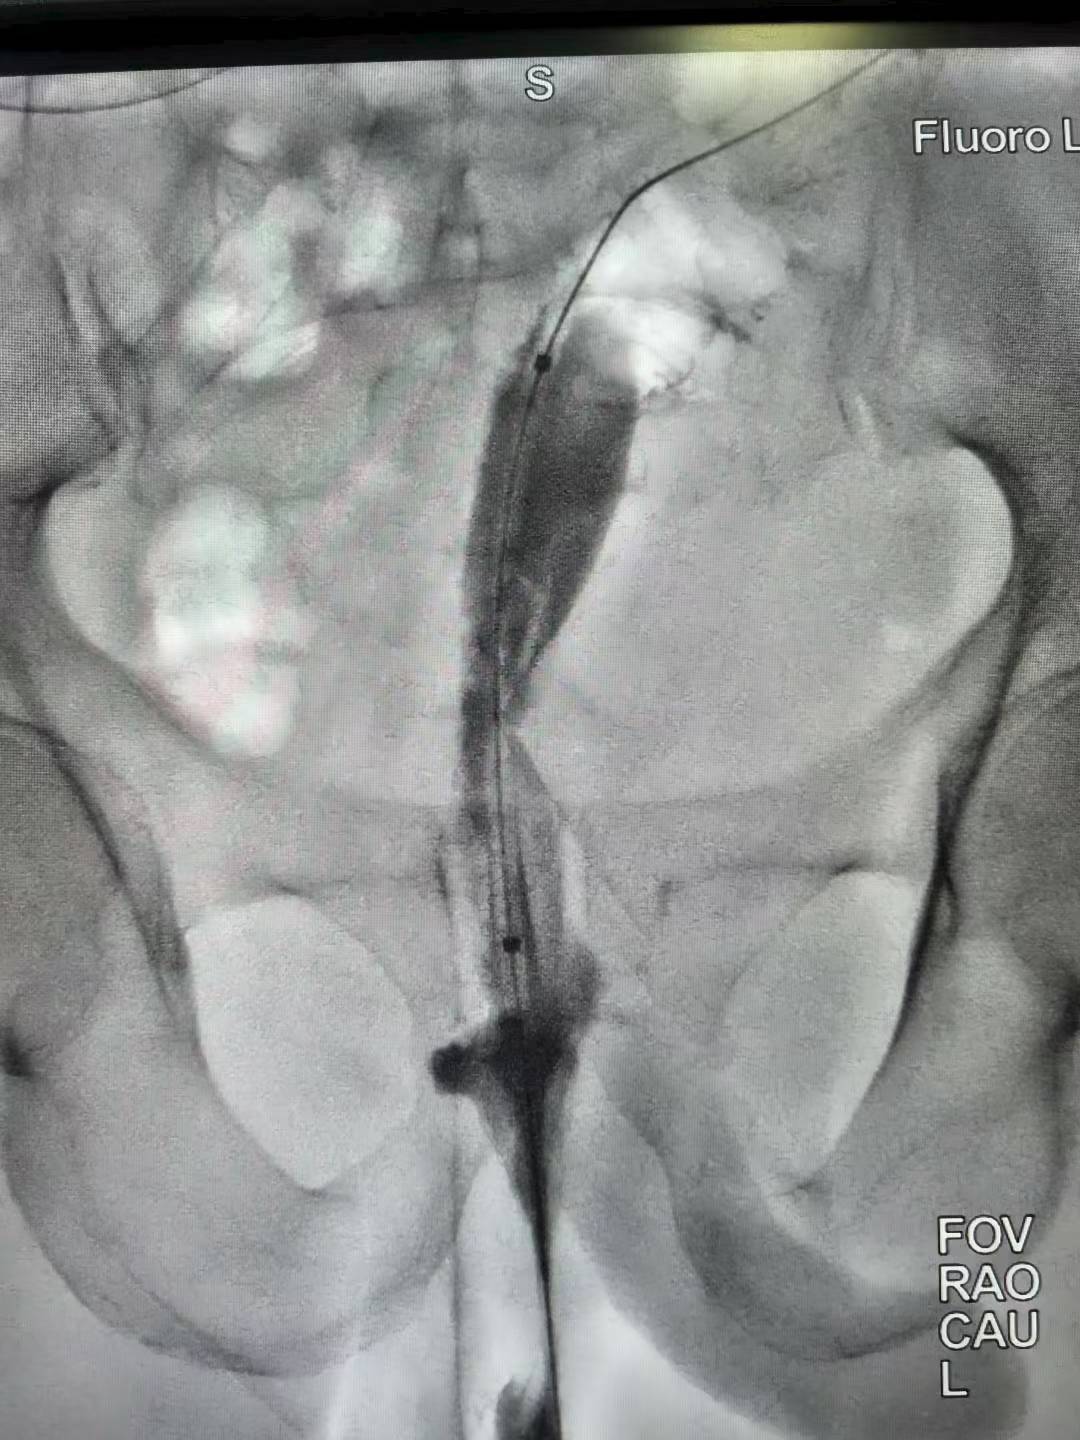

直肠癌术后吻合口狭窄(难治型)球囊扩张术。上午一台直肠癌术后吻合口狭窄经肛行球囊扩张术,球囊充分扩张后狭窄解除。介入球囊扩张对良性难治性狭窄,安全有效,术后即可排便顺畅。